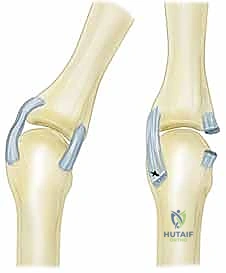

قبل الخوض في التفاصيل التقنية للإجراء الجراحي، من الضروري والمحوري أن نفهم البنية التشريحية المعقدة لمفصل MCP. هذا المفصل هو الرابط الحيوي بين عظام راحة اليد (الأمشاط - Metacarpals) وعظام الأصابع الأولى (السلاميات القريبة - Proximal Phalanges). يُصنف هذا المفصل على أنه مفصل لقمي (Condyloid Joint)، مما يعني أنه يسمح بحركات متعددة في مستويات مختلفة: الثني (Flexion)، البسط (Extension)، الانحراف الزندي (Ulnar Deviation)، الانحراف الكعبري (Radial Deviation)، بالإضافة إلى الحركة الدائرية المحدودة (Circumduction).

- الأربطة الجانبية الكعبرية والزندية (Radial and Ulnar Collateral Ligaments): هذه الأربطة حاسمة للغاية في توفير الاستقرار الجانبي. يتميز رأس العظم المِشطي بتأثير فريد يُعرف بتأثير "الحدبة" (Cam Effect)؛ حيث يزداد قطره وسمكه في المستويين العرضي والسهمي كلما اتجهنا نحو السطح الراحي. هذا التصميم الهندسي الإلهي يعني أن الأربطة الجانبية تكون مشدودة تماماً عند ثني الإصبع (مما يمنع الحركة الجانبية أثناء الإمساك بالأشياء)، وتصبح مرتخية نسبياً عند بسط الإصبع. هذا الارتخاء في وضع البسط هو ما يسمح لنا بفتح أصابعنا وإبعادها عن بعضها (انحراف كعبري وزندي).

- من المهم ملاحظة أن الأربطة الجانبية لمفصل MCP غير متماثلة. الرباط الجانبي الزندي يكون عادةً أكثر توازياً مع المحور الطولي للأصابع، بينما الرباط الجانبي الكعبري يكون أكثر ميلاً. هذا التباين التشريحي يساهم في حركة التفاف خفيفة (Supination) لمفصل MCP أثناء الثني.

- الأربطة الجانبية الإضافية (Accessory Collateral Ligaments): تقوم هذه الأربطة بربط الأربطة الجانبية الرئيسية بالصفيحة الراحية، مما يضمن بقاء الصفيحة الراحية ملتصقة بإحكام بالجانب الراحي (الباطني) لمفصل MCP طوال نطاق حركته الكامل.

- الرباط بين الأمشاط المستعرض (Deep Transverse Metacarpal Ligament): هذه الحزمة الليفية القوية تربط الصفائح الراحية للمفاصل الرسغية السلامية المجاورة ببعضها البعض، مما يوفر استقراراً عرضياً يمنع تباعد عظام المشط عن بعضها عند الإمساك بقوة.

- تمدد المحفظة والأربطة (Capsular Distension): التورم المستمر وتراكم السوائل والسبلة داخل المفصل يؤدي إلى تمدد وضعف المحفظة المفصلية والأربطة الجانبية، مما يفقد المفصل استقراره الثابت.

- الانزلاق الزندي للوتر الباسط (Ulnar Subluxation of EDC): بمجرد ضعف الرباط السهمي الكعبري، ينزلق وتر الباسطة (EDC) من أعلى قمة المفصل نحو الوادي الزندي بين الأمشاط. عندما يحدث هذا، يفقد الوتر قدرته على بسط الإصبع بفعالية، وبدلاً من ذلك، تصبح قوة سحبه مساهمة في زيادة الانحراف الزندي للأصابع.

- التصوير بالأشعة السينية (X-rays): لتقييم تآكل العظام (Erosions)، تضيق المسافة المفصلية (علامة على فقدان الغضروف)، ودرجة الخلع الجزئي.